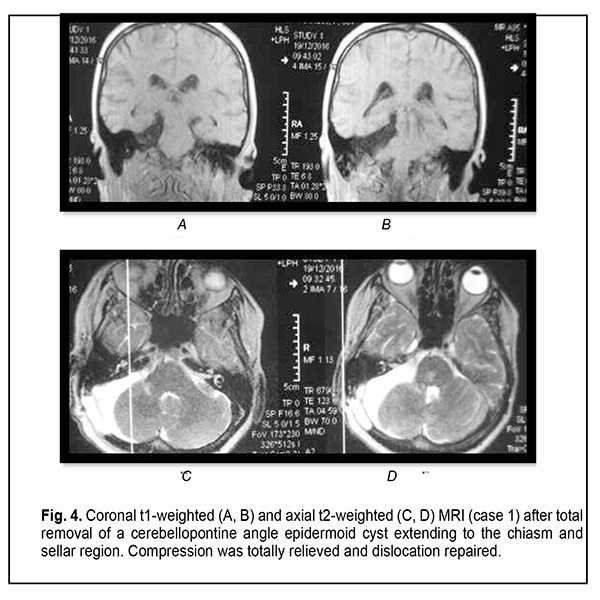

Introduction Epidermoid cysts manifest themselves clinically predominantly between the ages of 20 and 50 years, most commonly occur in the skull base, and usually arise in the subarachnoid cisterns, cerebellopontine angle and parasellar region. They grow slowly and can attain a large size before the onset of neurological symptoms. As the neoplasm grows, it gradually presses on, displaces and envelops the cranial nerves (CN) and adjacent vessels, and frequently invaginates the brainstem, causing ophthalmological abnormalities and lesions of relevant CN (Fig.1, 2, 3) [1, 2, 3].

Of the 21 patients, 7 (33.33%) had a gross total removal and 2 (9.53%) had a near total removal of the cyst, with residual capsule fragments not exceeding 2-3 mm (Figs. 4, 5, 6, and 7). In addition, 12 (57.14%) had a subtotal removal of the cyst, with either intraoperative evidence of residual capsule fragments measuring from 2 mm to 10 mm, or postoperative MRI evidence of residual capsule fragments not exceeding 11 mm in the largest dimension. The capsule adhesion to surrounding neurocascular structure at the location where the dissection was difficult was seen in 18 patients (85.7%). In some cases, this can lead to the impossibility of safe total capsule dissection from the brainstem and cranial nerves. Postoperative follow-up ranged from 1 to 12 years, with mean and median values of 38.5 ± 4.8 months and 24 months, respectively (Fig. 8).

Results Of the 21 neoplasms, 7 (33.33%) were seen just to the right of the brainstem, including 2 (9.52%) that had a supratentorial extension; 9 (42.87%) were seen just to the left of the brainstem, including 3 (14.28%) that had a supratentorial extension; and 5 (23.8%) were located along the midline (cysts of the fourth ventricle). Of the 5 cysts (23.8%) that had a supratentorial extension, 2 (10%) extended to the middle and posterior fossa, with involvement of the chiasm and optic nerve. MRI-based neoplasm dimensions and volume varied from 24х22х18 mm до 54х57х44 mm and from 4.75 cm3 to 67 cm3, respectively, although volume estimation could not be accurate due to a complex shape and extension of epidermoids. Table 1 shows longitudinal changes in neuroophthalmological symptoms in patients who underwent surgical removal of a skull-base epidermoid cyst.